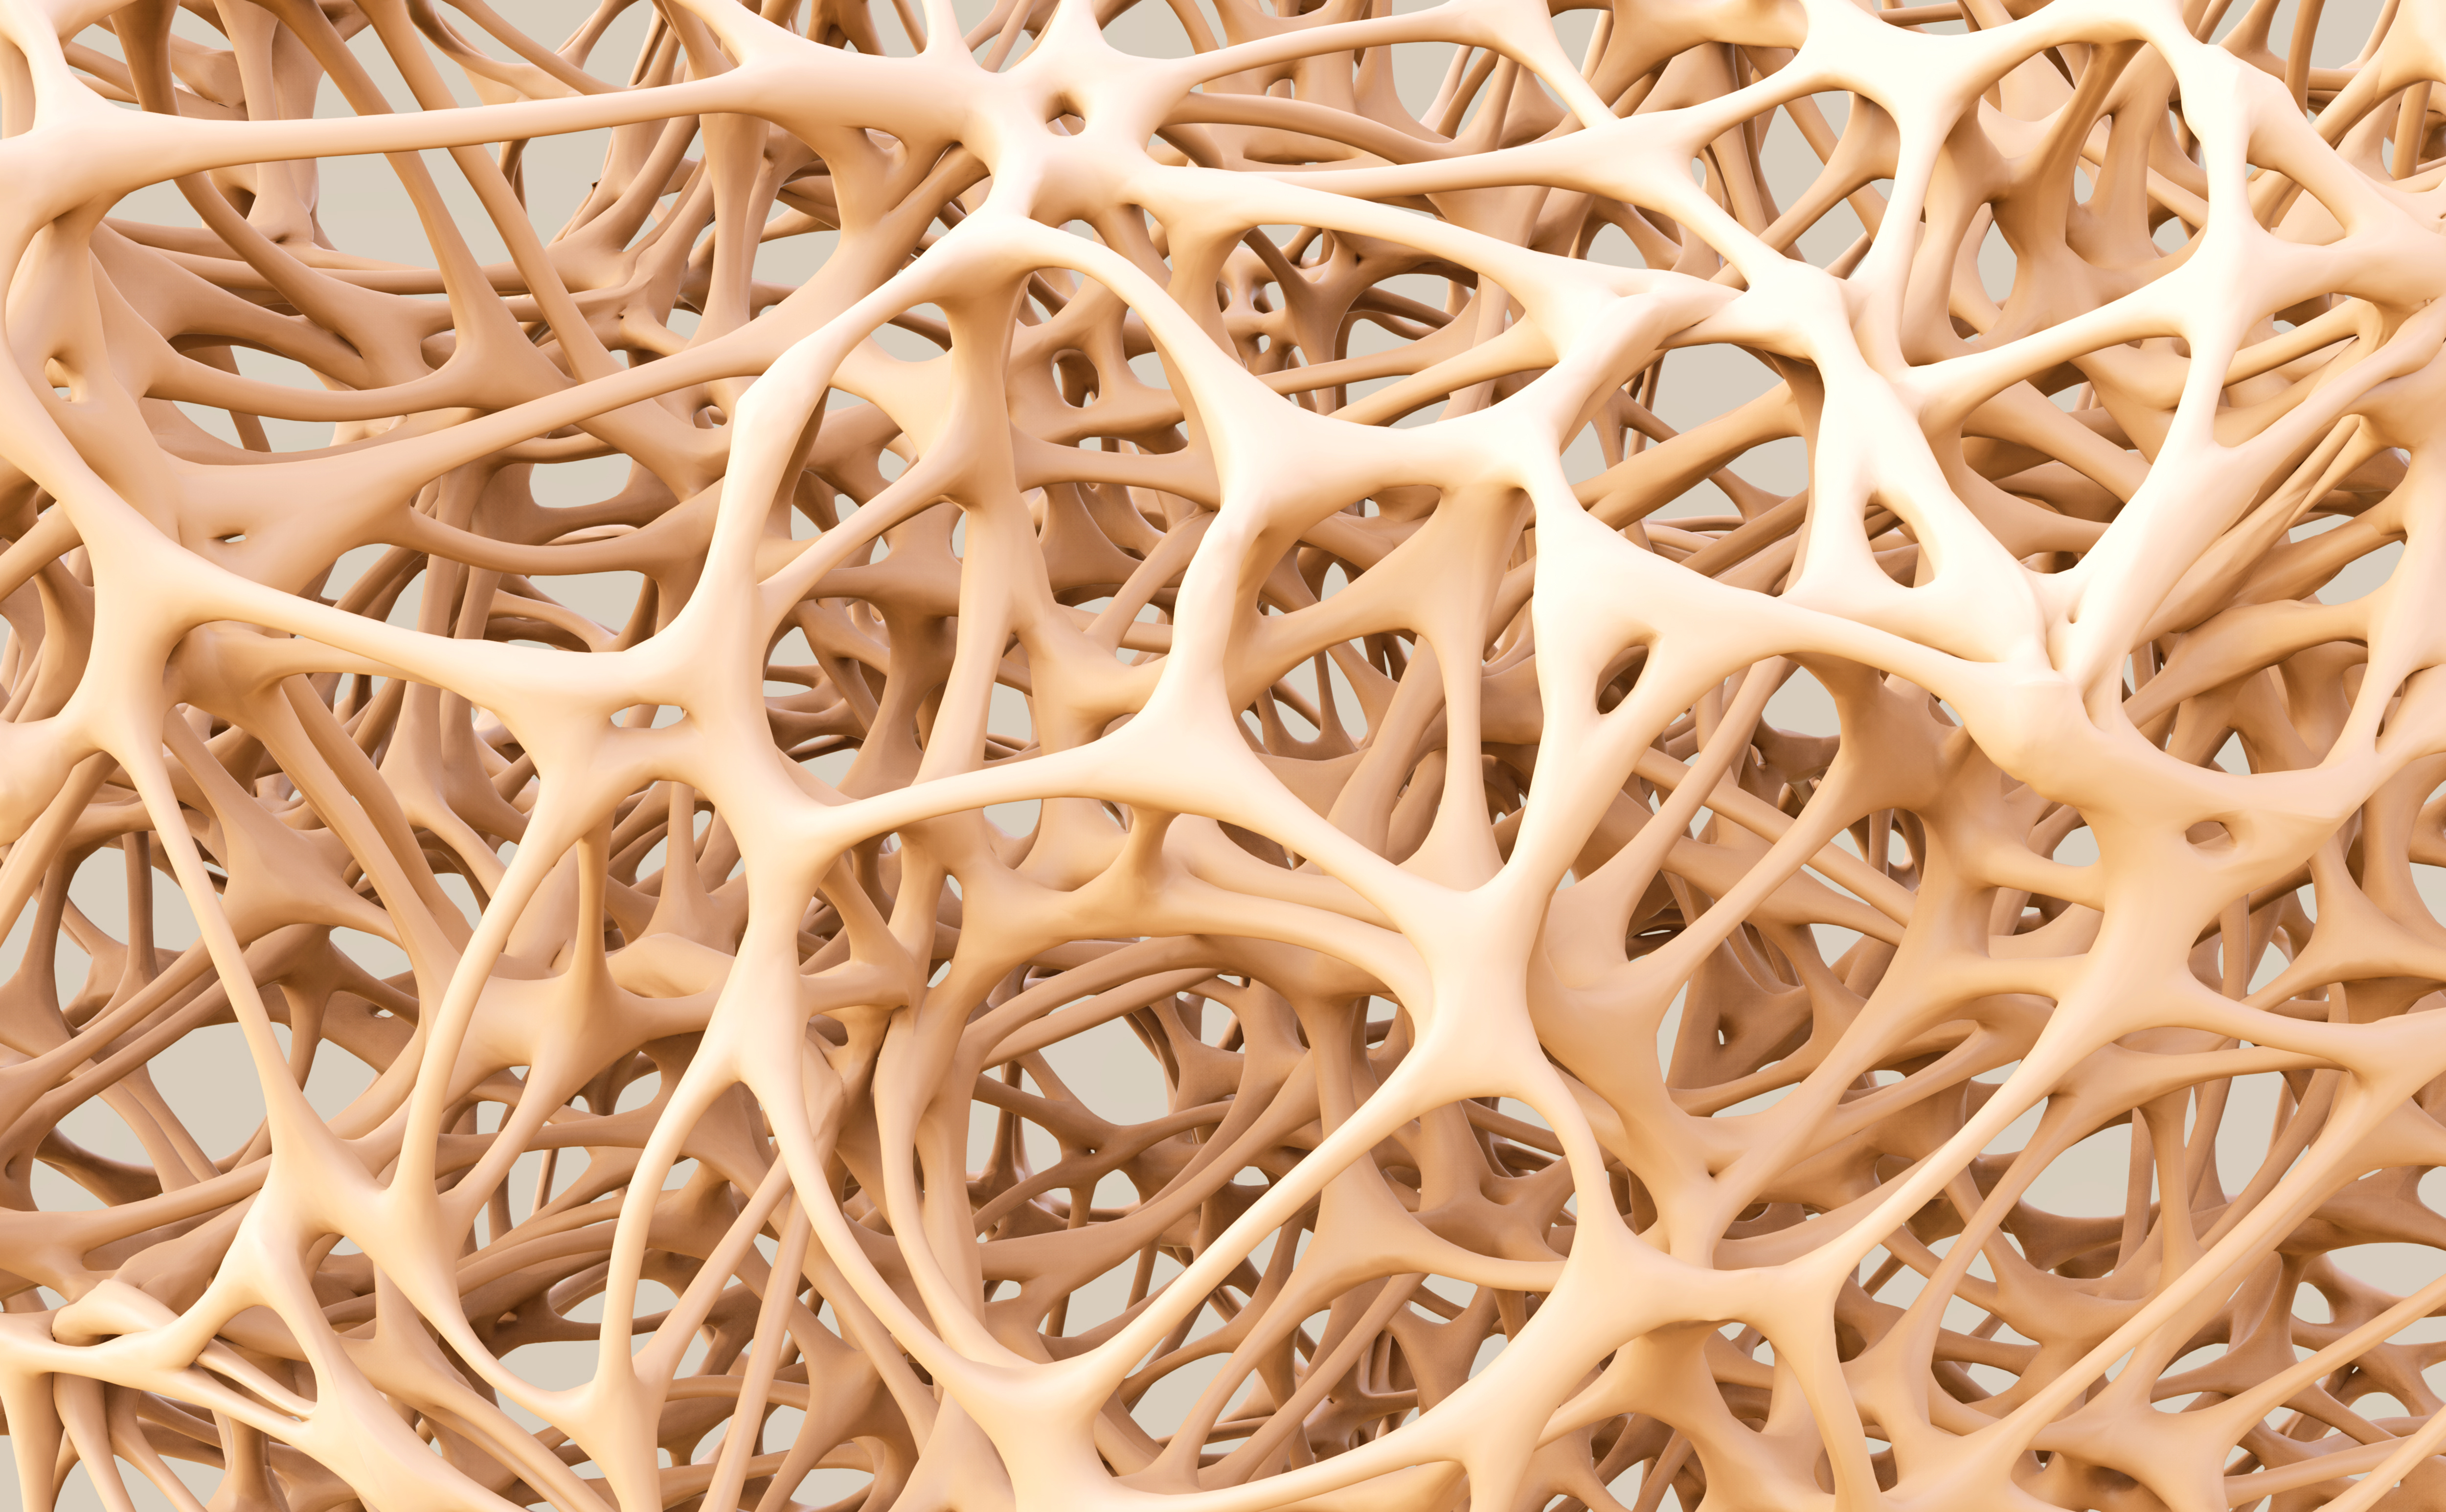

Структура грубоволокнистой костной ткани: наглядные примеры